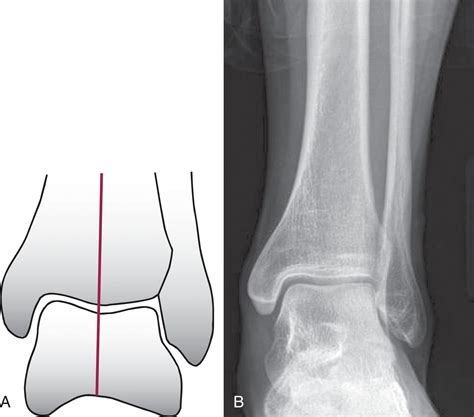

Ankle Arthritis and Arthrodesis - Clinical Tree